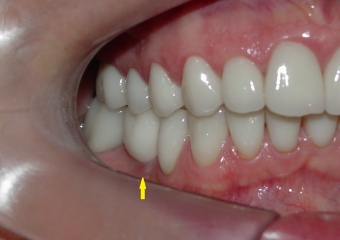

Sorriso inicial